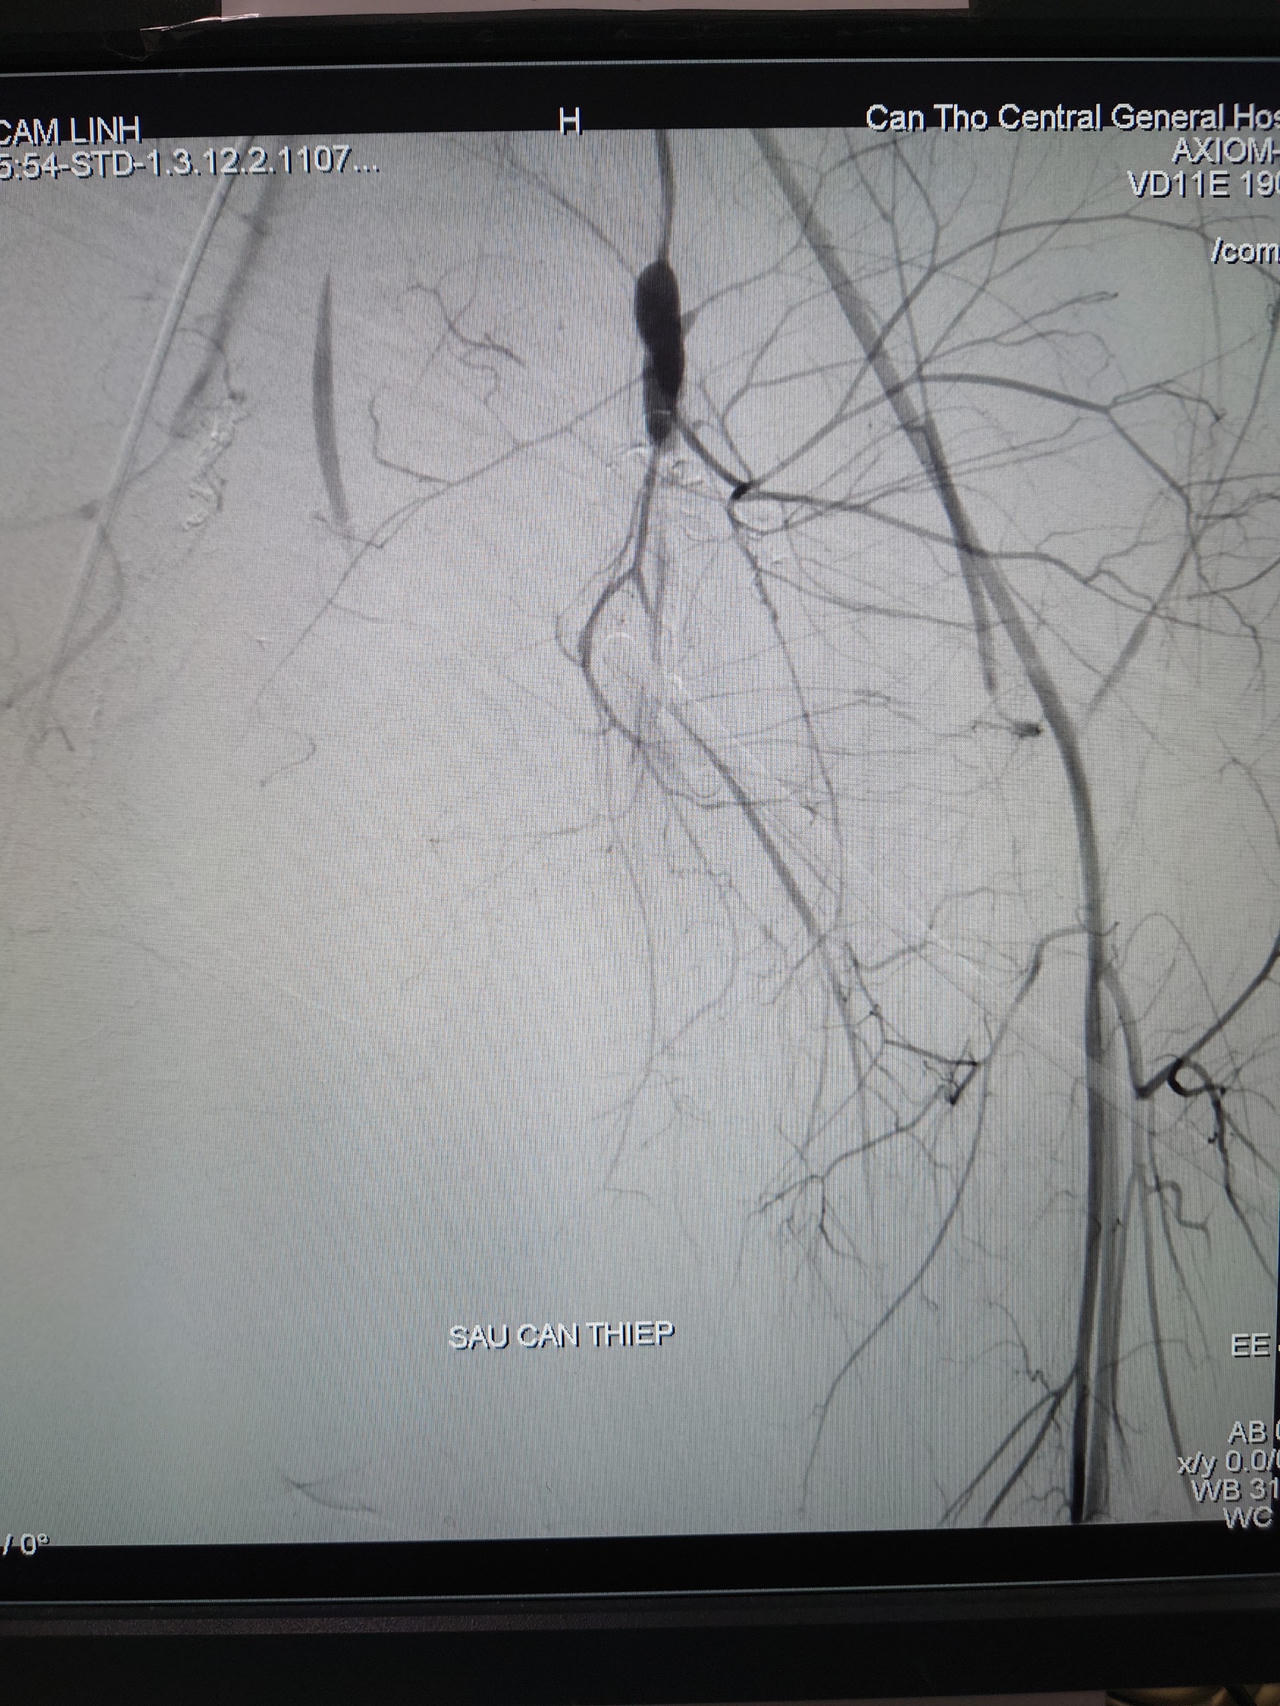

![]() |

Hình ảnh chụp mạch máu số hóa xóa nền sau can thiệp |